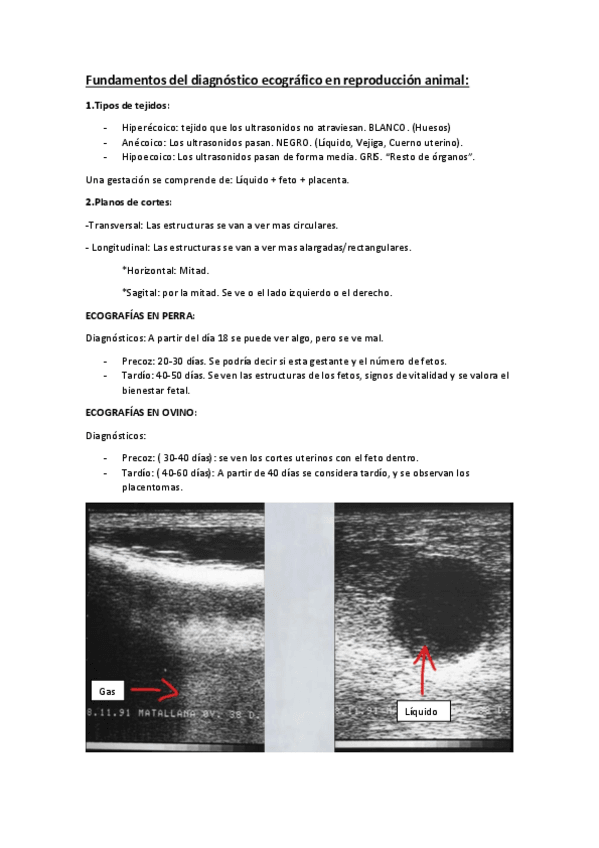

He publicado nuevos practicas de 3º Reproduccion y Fund. Obstetricos: Fundamentos-del-diagnostico-ecografico-en-reproduccion-animal.pdf